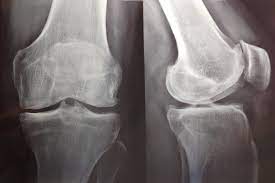

este nuevo análisis del estudio PRGF no encontró ningún beneficio clínica o estadísticamente significativo del plasma rico en factores de crecimiento (PRGF) en comparación con el ácido hialurónico. La restauración del Estudio PRGF muestra la urgencia de cambios importantes en las prácticas de supervisión e informes de juicios. En el futuro, se necesita acceso oportuno a todos los documentos de ensayos clínicos para minimizar el riesgo de sesgo de informe. Del mismo modo, los comités de ética deben estar listos para intervenir cada vez que surja un caso de posible mala conducta. Trials, 18 de enero de 2023